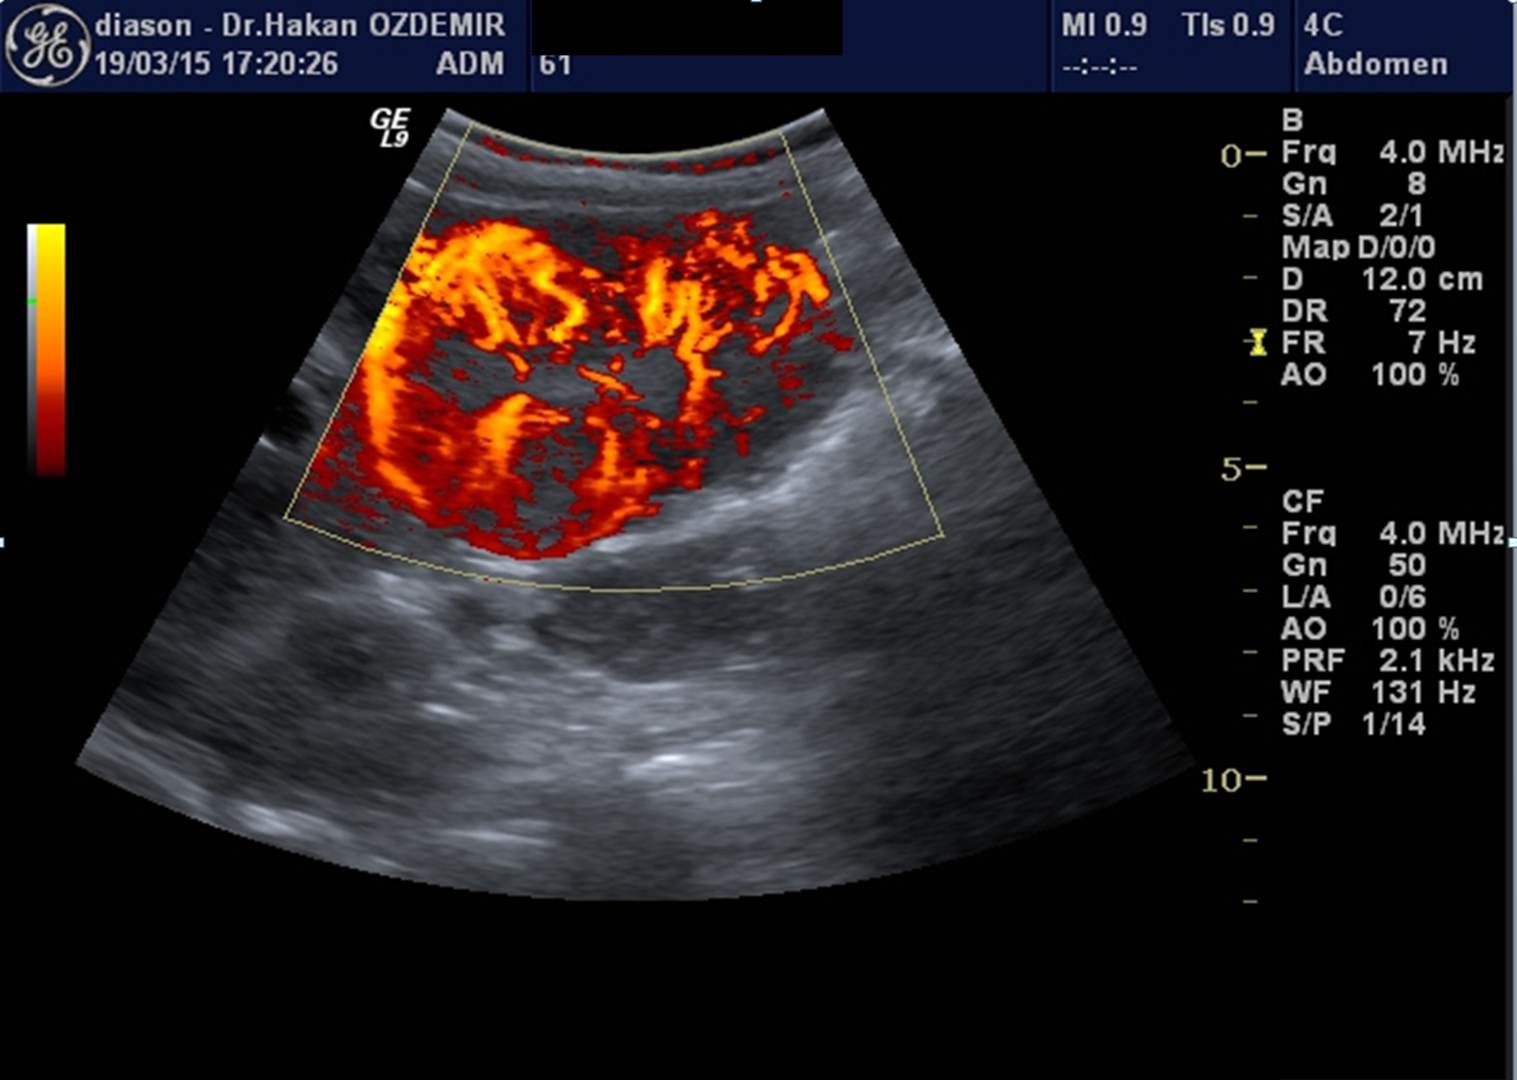

ABDOMİNAL AORTA (karındaki ana atar damar) RENKLİ DOPPLER ULTRASON

Karından geçen ana atar damar ve ana dalları incelenir.